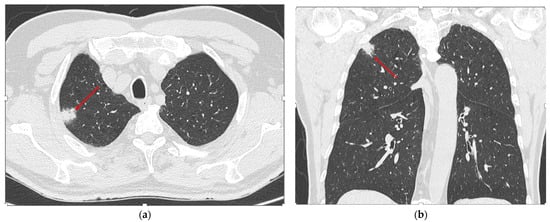

2.3. Imaging Analysis